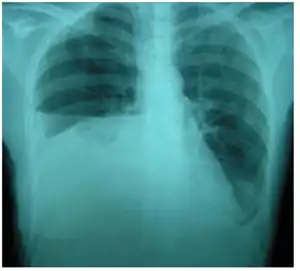

| Bilateral pleural effusions caused by urinothorax. | |